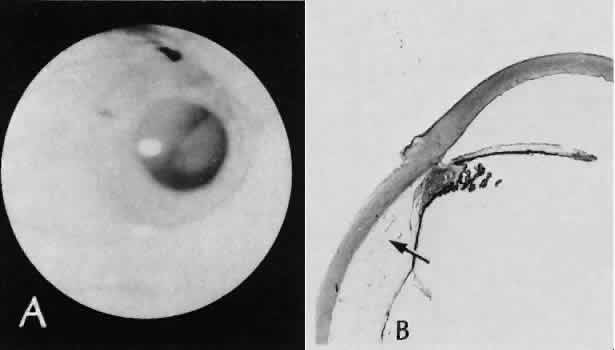

| All ocular surgical procedures are associated with potential complications. A

complication is a deviation from the natural course of the expected

tissue response after a surgical procedure and, in the case of ocular

surgery, usually results in a compromise of ocular function. Complications

may arise from the surgical procedure itself or be the result

of an aberration of the wound healing process. All surgeons will encounter

surgical complications. Eyes afflicted with severe or multiple

disease processes are more likely to develop complications. Early recognition

and a thorough understanding of these deviations from normal allow

for more effective therapeutic intervention.86 Many complications originate from so-called surgical confusion (Fig. 24). Most arise from a lack of knowledge, a lack of judgment, or problems in perception. At times, lack of attention to detail in preoperative planning may lead to a drug reaction, inadequate anesthesia, misplacement of incisions and sutures, or a patient who is unable to control a cough reflex. What is recognized histologically as the immediate cause of the problem may well have its origin in improper planning of the procedure. CATARACT EXTRACTION Intraoperative Complications Complications occurring from the time the patient enters the operating room until the patient leaves the operating room are considered intraoperative.87,88 Misplacement of an anterior segment incision too far anteriorly into the cornea may create an unacceptable degree of scarring or astigmatism, whereas misplacement too far posteriorly (Fig. 25) may cause the incision to enter the ciliary body instead of the anterior chamber, an especially serious event in glaucoma filtering procedures. Misplacement oflimbal sutures (Fig. 26) may cause anterior wound gaping if placed too far posteriorly or posterior wound gaping if placed too far anteriorly. A deep suture may enter the anterior chamber and lead to wicking and a flat anterior chamber postoperatively. A suture placed at different depths in the two sides of the wound results in faulty apposition of the wound edges. Descemet's membrane is only loosely adherent to the posterior stroma and may be stripped into the anterior chamber at the time of the corneal incision placement (Fig. 27) or injection of sodium hyaluronate. Splitting off of Descemet's membrane from the posterior cornea can lead to postoperative intractable corneal edema.89,90 Intraoperative anterior chamber hemorrhage may result from an inadvertent iridodialysis or from the iridectomy wound. The site of hemorrhage is usually found along the scleral side of the cut edge of the wound. This type of hemorrhage rarely leads to serious clinical problems.91 Rupture of the posterior lens capsule (Fig. 28) increases the risk of vitreous loss and limits options for the implantation of an intraocular lens. Retention of lens capsular tissue or vitreous in the wound (Fig. 29) will significantly delay the wound healing process. Vitreous loss leads to an increased incidence of iris prolapse, bullous keratopathy, epithelial downgrowth, stromal overgrowth, wound infection and endophthalmitis, updrawn or misshapen pupil, vitreous bands, postoperative flat anterior chamber, secondary glaucoma, retinal detachment, cystoid macular edema, optic disc edema, vitreousopacities, vitreous hemorrhage, and other sight-threatening consequences.92 Damage to the endothelium during insertion or positioning of the lens was one of the most common problems with intraocular lens implantation until the widespread use of intraoperative viscoelastics. The endothelial cell damage may manifest on the first postoperative day as corneal edema. The course of the edema may wax and wane and ultimately result in pseudophakic bullous keratopathy months or years after surgery. Detachment of Descemet's membrane, inadvertent iridodialysis, cyclodialysis, or rupture of the posterior capsule also may occur during lens insertion and positioning. Expulsive choroidal hemorrhage (Fig. 30) is a rare catastrophic complication often resulting in total loss of the eye.93 The site of hemorrhage is probably a sclerotic choroidal arteriole where the vessel crosses the suprachoroidal space from the scleral canal. The sudden hypotension after surgical penetration of the globe causes a bending and then a rupture of the arteriole.94 Although most hemorrhages are massive and immediate, they occasionally are delayed, and some may not occur for days or weeks after surgery. Delayed choroidal hemorrhage may occur at the time of corneoscleral suture removal,95 because of clinically unapparent wound dehiscence or as a result of perforation of a corneal ulcer. Histologically, massive choroidal hemorrhagic detachment is associated with a retinal detachment. The retina and choroid may herniate through the scleral wound. A ruptured ciliary artery may be found in the suprachoroidal space. Postoperative Complications Postoperative complications may arise from the time the patient leaves the operating room until approximately 6 weeks after surgery.96 A flat anterior chamber is characterized by anterior displacement of the iris to near or in actual contact with the posterior surface of the cornea. The most common cause is leakage of aqueous along one of the suture tracks. Prolonged decompression of the anterior chamber increases the risk of synechiae formation and intractable secondary closed-angle glaucoma. Corneal endothelial damage may result in bullous keratopathy. Choroidal edema (choroidal hydrops or detachment) (Fig. 31) may be associated with a flat anterior chamber and may potentiate the condition. The choroidal edema will slow or stop aqueous production by the ciliary body, further delaying reformation of the anterior chamber. The histologic characteristics of choroidal edema consist of spreading of the choroidal tissue in a fanlike configuration and eosinophilic fluid filling the intervening spaces. The edema fluid may be lost in processing, leaving multiple apparently empty spaces. Iris or lens capsular incarceration into the wound and extending to the conjunctival space (Figs. 32 and 33) may act as a wick through which aqueous can escape, causing a flat anterior chamber. Histologically, iris, which is frequently recognized only by the presence of melanocytes, is seen in the limbal scar, in the limbal episclera, or in both areas. Vitreous wick syndrome consists of vitreous incarceration in the wound, where the vitreous may extend beyond the wound to the subconjunctival space or occasionally to the ocular surface.97 Anchoring of the vitreous anteriorly in this manner may lead to extensive intraocular inflammation even in the absence of infection. The vitreous may act as a conduitfor bacteria, leading to bacterial endophthalmitis.98–100 Pupillary block glaucoma results from isolation of the posterior chamber from the anterior chamber. Occasionally, even in the presence of a clinically patent peripheral iridectomy or iridotomy, the aqueous cannot exit into the anterior chamber. The block results from contact of formed vitreous, lens remnants, or intraocular lens material with the posterior surface of the iris.101,102 The area of contact may include the iridectomy or iridotomy site. Prolonged contact with any of these tissues or materials will cause posterior synechiae formation. After complete posterior synechiae formation, peripheral anterior synechiae develop. Pupillary block glaucoma (closed-angle glaucoma) may not be clinically evident until aqueous production returns to normal levels after surgery. The intraocular lens may be a stimulus for ongoing uveitis, hyphema, and glaucoma (UGH syndrome) (Fig. 34) through multiple factors.103,104 Although lens manufacturing has improved since the early days of fabrication, retained polishing compounds or burrs and irregular surfaces of the lens or loops may cause a low-grade, sterile endophthalmitis.105 Most intraocular lens materials, with the exception of polymethylmethacrylate, have been shown to stimulate some degree of inflammation, which in turn may cause biodegradation of the lens material.106 Several epidemics of lenses contaminated with fungus have been reported. Intermittent movement or continuous pressure of the intraocular lens material against ocular tissue often will result in focal necrosis, tissue disruption, or microhyphema, which may lead to fibrous scarring. This is particularly important when the tissues of the anterior chamber angle are in contact with an anterior chamber lens. Posterior lens loops may erode the iris pigment epithelium and give rise to a type of pigmentary dispersion syndrome (Fig. 35).107,108 Lenses directly supported by the iris have caused lacerations of the iris because of continuous compression by metallic loops (see Fig. 35).109 Iris-supported intraocular lenses are associated with a high incidence of dislocation and subsequent damage to the eye. Corneal endothelial decompensation (Fig. 36) may lead to bullous keratopathy at almost any time in the postoperative period, depending on the state of health of the endothelium at the time of surgery and the extent and nature of injury to the endothelial cells.110,111 Corneal edema may present early in the postoperative period when the cornea has been compromised by advanced Fuchs corneal dystrophy. If the endothelial cells are healthy and the intraoperative trauma is minimal, the signs of decompensation may not appear for decades. Endothelial damage may be the result of mechanical contact with surgical instruments or an intraocular lens, a toxic reaction to solutions used intraoperatively, poor tissue handling techniques, or prolonged and intensive postoperative inflammation.112 Histologically, the corneal epithelium is generally thinned. There may be areas of intraepithelial basement membrane and cyst formation, resulting from malorientation of the squamous epithelial cells during recovery from multiple episodes of bullous separation from Bowman's membrane (Fig. 37). Bullous separation of the epithelial cells varies in extent but is almost always present. Focal areas of interruption of Bowman's membrane and anterior corneal stroma scarring will mark rupture of bullae and subsequent ulceration. In chronic cases, extensive degenerative pannus formation is often seen. The corneal stroma may show a decreased density of keratocyte nuclei. A decrease in or absence of the artifactual clefts of the corneal stromal lamellae suggests edema of the stroma. Descemet's membrane may be focally or diffusely thickened with preexisting Fuchs corneal dystrophy (Fig. 38). In most cases, Descemet's membrane is normal in character and thickness. Often the corneal endothelial density is reduced to the point that only an occasional endothelial cell nucleus can be seen. Infectious bacterial endophthalmitis (Figs. 39 and 40) usually presents early in the postoperative period.113,114 Pseudomonal and streptococcal organisms often cause rapid and total destruction of the eye. Organisms of especially low virulence, such as Staphylococcus epidermidis and Priopionibacterium acnes, may not present for months and may be misinterpreted as sterile endophthalmitis caused by a toxic reaction to intraocular lens materials or phacoanaphylactic endophthalmitis targeted to lens cortical remnants.115–117 Infectious endophthalmitispresenting months after surgery may be caused by a fungal infection or by bacteria of low virulence as pointed out above. Delayed Complications Delayed complications are those that occur more than 6 weeks after surgery. These complications include corneal endothelial decompensation and delayed infectious endophthalmitis, as discussed previously. Elschnig's pearls (Fig. 41) result from aberrant attempts by lens cells attached to the lens capsule to form new lens “fibers.” Histologically, large, clear lens cells (“bladder cells”) are present behind the iris, in the pupillary space, or in both areas. Soemmerring's ring cataract results from the loss of anterior and posterior cortex and nucleus but with retention of equatorial cortex. Apposition of the central portions of the anterior and posterior lens capsule causes a doughnut configuration. Frequently, the doughnut is not complete, so that C- or J-shaped configurations result. Histologically, two balls of trapped and proliferated lens cells are encapsulated behind the iris leaf and connected by adherent anterior and posterior lens capsule in the form of a dumbbell.118 Delayed complications of intraocular lenses themselves are infrequent. The incidence of posterior capsular opacification ranges between 11% and 46% in this period, apparently lower in the presence of an intraocular lens than with extracapsular cataract surgery alone.119,120 Histologically, residual lens epithelial cells are transformed into cells with myofibrillar contractile properties, which wrinkle and opacify the posterior capsule and synthesize the extracellular matrix. Retinal detachment (Fig. 42) occurs in approximately 2% to 8% of intracapsular cataract surgeries, compared with approximately 0.0013% in the general population. The incidence of retinal detachment after extracapsular cataract extraction and posterior chamber lens implantation ranges between 0.6% and 1.5%.121 Vitreous loss increases the incidence of postoperative detachments, particularly if there is vitreous incarceration into the cataract wound. The character of the retinal detachment is independent of the type of cataract surgery or the type of intraocular lens implanted. However, a lower incidence of proliferative vitreoretinopathy appears in cases of extracapsular cataract extraction than was formerly seen with intracapsular cataract extraction. Aphakic or pseudophakic glaucoma122,123 is a nonspecific term referring to a pathologic and sustained increase in pressure after surgery for removal of cataract. In the delayed phase, this glaucoma is mainly caused by secondary chronic angle closure. However, a preexisting predilection to simple open-angle glaucoma may be the cause. Circumferential peripheral anterior synechiae may develop from persistent flat anterior chamber. Focal synechiae are often found adherent to the posterior aspects of the surgical incision. Histologically, the iris is apposed to the posterior cornea, often central to Schwalbe's ring. Posterior synechiae are generally the result of posterior chamber inflammation (caused by iridocyclitis, endophthalmitis, or hyphema) causing iris bomb, and secondary peripheral anterior synechiae (Fig. 43). Histologically, the posterior pupillary portion of the iris is adherent to the anterior face of the vitreous, to the lens remnants, to the intraocular lens, or to all three structures. The anterior peripheral iris is adherent to the posterior cornea (peripheral anterior synechiae), frequently central to Schwalbe's ring. Epithelial downgrowth (ingrowth) (Fig. 44) is one of the most serious causes of pseudophakic glaucoma, in which surface epithelium (probably from the conjunctiva) grows into the anterior chamber. This condition is more likely to occur with fornix-based conjunctival flaps than with limbus-based flaps and in eyes with problems in wound closure, such as vitreous loss, wound incarceration of tissue, delayed reformation of the anterior chamber, or frank rupture of the limbal incision, and when instruments such as iridectomy forceps are contaminated with surface epithelium before they are introduced into the eye. Epithelial downgrowth causes an anterior chamber angle closure by means of peripheral anterior synechiae or lines an open anterior chamber angle and obstructs aqueous outflow mechanically. Histologically, the epithelium is seen to grow most luxuriously and in multiple layers on the iris where there is a good blood supply, but it tends to grow sparsely and in a single layer on the posterior surface of the avascular cornea. The epithelium may extend behind the iris, over the ciliary body, and even far into the interior of the eye. Iris cyst formation (Figs. 45 and 46 is also caused by implantation of surface epithelium onto the iris at the time of surgery or trauma. The cyst generally grows slowly and is accompanied by peripheral anterior synechiae. If extensive, the cysts may cause a secondary chronic closed-angle glaucoma. Histologically, the cyst is lined by stratified squamous or columnar epithelium, sometimes containing mucous cells, and is filled with keratin debris (white or pearly cysts) or mucous fluid (clear cysts). Stromal overgrowth (Fig. 47) is a condition characterized by growth of fibrous connective tissue into the anterior chamber. It is most likely to occur after vitreous loss or tissue incarceration into the surgical wound. The overgrowth may be localized, may be limited to the area of surgical perforation of Descemet's membrane, or may be extensive. When overgrowth is extensive, peripheral anterior synechiae and secondary closed-angle glaucoma result. As with epithelial downgrowth, the stromal overgrowth may extend behind the iris, over the ciliary body, and far into the interior of the eye. Histologically, fibrous tissue generally extends from the corneal stroma or is in continuity with it, through a large gap in Descemet's membrane. The fibrous tissue often covers the posterior cornea, fills part of the anterior chamber, occludes the anterior chamber angle, and may extend into the vitreous compartment to attach posteriorly onto the retina. Bacterial inflammation is rare in the delayed period after surgery, except after filtering procedures in which bacteria can gain access to the inside of the eye by way of the bleb (Fig. 48). Another exception to this rule is Priopionibacterium acnes or Staphylococcus epidermidis endophthalmitis, which infects lens remnants and may not clinically manifest for many months after cataract extraction. Fungal endophthalmitis (Fig. 49) may take the form of keratitis or endophthalmitis. Histologic characteristics of end-stage endophthalmitis include fibrovascular organization centered about a chronic nongranulomatous inflammatory reaction contiguous with lens remnants, causing cyclitic membrane formation and retinal detachment. Multiple small foreign bodies, inadvertently introduced at the time of surgery, can cause a delayed chronic nongranulomatous or granulomatous inflammatory reaction. Phacoanaphylactic endophthalmitis or sympathetic uveitis may occur after extracapsular cataract extraction (discussed elsewhere in these volumes). Healed cataract wounds may rupture because of trauma. In particular, blunt trauma to the eye may cause ocular rupture, often at the site of a cataract scar that remains weaker than surrounding tissue. Cystoid macular edema, or Irvine-Gass syndrome, is an inflammatory, degenerative condition of unknown cause that involves primarily the macula and leads to temporary or permanent loss of macular function. This condition can occur anytime after cataract surgery (even up to 5 years), but most cases occur within 2 months of surgery. The initial clinical sign is a sudden decrease in visual acuity. At least 50% of the cases are self-limiting, and the macular edema resolves completely, with or with-out therapy, within 1 year. Most patients experi-ence spontaneous recovery of vision. In a few cases,however, the intraretinal edema may persist, andsecondary permanent complications, such as lamel-lar macular hole formation, may occur. The condi-tion can be precipitated or aggravated by topicalepinephrine therapy for glaucoma. The cause ofcystoid macular edema is unknown, but in somecases (probably the minority), vitreous traction or aposterior vitritis may play a role (Fig. 50). Histo-logically, iritis, cyclitis, retinal phlebitis, and retinal periphlebitis have been noted. Whether these conditions cause the cystoid macular changes or are simply incidental findings in enucleated eyes is not clear. A lamellar macular hole may occur as a permanent complication. Ophthalmoscopically (best seen with a slit-lamp biomicroscope), multiple (usually four or five) intraretinal microcysts are seen in the macular area, obscuring the normal foveal reflex. The cysts fill early with fluorescein, and pooling causes a characteristic stellate geometric pattern that persists for 30 minutes or longer. Granular fluid is seen in the microcystic spaces (Fig. 51). The anatomic basis of early cystoid macular edema probably is edema of Müller cells; later, Müller cell membranes break down and the edema becomes extracellular. PENETRATING KERATOPLASTY Immediate Complications Complications of penetrating keratoplasty may arise in the selection of donor material. The success of a graft depends on the health and integrity of the donor endothelium. Compromise of endothelial function attributable to the age of the donor, preexisting endothelial disease (Fuchs corneal dystrophy), toxicity of storage procedures, microbial infection, or intraoperative trauma will lead to early endothelial decompensation. Immunologic testing and a careful history of infectious disease of the donor (AIDS, hepatitis, Jakob-Creutzfeldt disease, and rabies) are essential because the virus may be harbored in the donor tissue. Retention of significant amounts of host Desce-met's membrane and presence of nonviable peripheral host tissue in patients with alkali burns are additional potential intraoperative problems. Improper apposition of the donor-host interface may lead to multiple structural and refractive problems. Overriding of the wound edge is a likely site for wound leak, leading to a flat anterior chamber, which in turn may lead to central anterior synechiae to the wound or total anterior synechiae. Malposition of the posterior wound edge is likely to enhance fibrous tissue proliferation, which may remain in the local region of wound or may spread peripherally or even centrally (stromal in growth). Postoperative Complications Penetrating keratoplasty has the same risks for microbial infection, epithelial ingrowth, stromal ingrowth, and expulsive choroidal hemorrhage, as does anterior segment surgery in general. Immune rejection of a corneal graft is an unusual complication, except when the host tissue is extensively vascularized. Immune stromal graft rejection clinically manifests 2 to 3 weeks postoperatively and is heralded by inflammatory signs associated with progressive vascularization of the graft. Histologically, a central necrotic area is bounded peripherally by a zonal inflammatory response. Polymorpho-nuclear leukocytes predominate near the necrotictissue, surrounded by a zone of lymphocytes and plasma cells. The endothelial layer may undergo specific graft rejection. This is recognized clinically as a centrally advancing, linear, posterior corneal opacity (Khoudadoust's line). Histologically, there is a chronic nongranulomatous inflammatory reaction about necrotic endothelial cells. Delayed Complications Graft failure is a nonspecific term used to indicate progressive or persistent opacification of a donor cornea. In most cases, the histologic characteristics are those of corneal endothelial decompensation. In some cases, particularly those with underlying systemic disease or ocular surface abnormalities, there may be extensive corneal ulceration or perforation. REFRACTIVE SURGERY Immediate Complications Accidental perforation of the globe is possible with any of the refractive procedures. Variability of the incision depth is one of the most important factors in the ultimate variability of the refractive correction obtained by the procedure. Postoperative Complications Microbial endophthalmitis, even leading to blindness, has been reported as a complication of this type of procedure. There appears to be an acute postoperative endothelial cell loss that is not progressive. Wound healing of radial keratoplasty has been complicated by intrastromal epithelial cyst formation and a generalized decrease in the rate of healing of the incision (Fig. 52). Complete healing and refractive stability may not be realized for years. Epikeratophakia procedures have been complicated by delayed reepithelialization of the grafted tissue and epithelial retention or proliferation along the interface between the lenticule and the host tissue. Persistent folding of Bowman's membrane underlying the grafted tissue and abnormal keratocytes in the underlying recipient stroma may lead to a poor visual result. In some cases, the lenticule of keratomileusis has been slow to be repopulated by host keratocytes, which may be responsible for persistent opacification of the grafted area. Thickening of the epithelial basement membrane, a decreased density in hemidesmosomes, and abnormalities of Bowman's membrane have been observed. Abnormal proteoglycan synthesis also has been suspected in these cases. Visually significant opacities at the tissue-synthetic material interface have been noted with corneal intrastromal inlay procedures (Fig. 53). This material, which has been found to contain lipid, appears to accumulate over time. Corneal inlays of all types have been complicated by necrosis of the tissue overlying the pocket and extrusion of the synthetic material. Delayed Complications An early type of radial keratotomy, which included incisions of the internal surface of the cornea, has resulted in a high degree of corneal endothelial decompensation 20 years after the procedure, regardless of the age of the patient at the time of surgery. LASIK Complications of LASIK Variability in actual flap thickness has also been noted in several studies. The lack of uniformity of flap dimensions may be important in repositioning the flap in the stromal bed.124 Microfolding of the anterior corneal flap was found in 94% of eyes examined by confocal microscopy. The folding was attributed to stretching of the tissue during laminectomy or to imprecise registering of the flap tissue with the lamellar bed.75 The character of the blade edge, particularly of a blade that has been used for more than one procedure, also influences the morphology of the stromal incision. Notching of the blade profile with repeated use has been observed by scanning electron microscopy. Notching of the blade edge also appears to be associated with accumulation of tissue remnants on the surface of the blade.67,68 The tissue remnants can be identified as reflective interface particles by confocal microscopy. Potential sources of the material include metal from the microkeratome blade, cotton, lipid, inflammatory cells, intact epithelial cells, or remnants.75 Complications occur in approximately 3% to 5% of LASIK procedures.78,125,126 Intraoperative compilations are primarily related to creation of the lamellar flap. Included among this type of complication are flap irregularities, epithelium and other material within the lamellar interface, regular and irregular astigmatism, flap loss, displacement, and button-holing. Infection is a rare but potentially serious complication.78,127–131 Perforations of the globe have been described.132–137 Potential complications at 6 months include epithelial ingrowth, corneal flap melting, decentered ablation, and irregular astigmatism with loss of best-corrected visual acuity.124 Complications related to abnormal endothelial cell function have been infrequent.134,138–140 Progressive epithelial ingrowth may occur characterized as a continuous sheet of epithelium contiguous with the flap edge (Fig. 54).124,141 Epithelial ingrowth into the intrastromal interface may be associated with enzymatic digestion of the cornea.142 Diffuse interface keratitis is a condition char-acterized by acquired opacification at the level ofthe intralamellar bed after a LASIK procedure(Fig. 55).143 Many causes of the syndrome have been reported144–147 and include exotoxins released from sterilizer reservoir biofilm148 and debris on the microkeratome blade149 and methylcellulose sponge material.150 Most cases resolve spontaneously.151 The resistance of eyes to trauma after LASIK, even in the absence of healing appears to be similar to unoperated human eyes as evaluated in a model of postmortem refractive procedures performed on autopsy eyes.152 In this model, radial keratotomy incisions predisposed rupture at lower energy levels than in unoperated eyes.153 Postoperatively, there was a decrease in intraocular pressure measured by central tonometry that was statistically significant. Differences in pneumotonometry were less substantial, with greater reliability of pneumotonometry than Goldmann applanation tonometry after LASIK.154 GLAUCOMA SURGERY Immediate Complications Creation of a button hole in the conjunctiva is not serious in cataract surgery but may lead to failure in filtering procedures. Misplacement of the incision too far posteriorly may cause the incision to enter the ciliary body instead of the anterior chamber, an especially serious event in glaucoma filtering procedures. Postoperative Complications Cataract formation may be caused or accelerated by glaucoma surgery, even if the lens is not apparently damaged by physical contact. The cataract may be a result of shunting of the aqueous through the iridectomy, so that the anterior and posterior surfaces of the lens are not properly nourished. Bacterial endophthalmitis may occur. Hypotony and choroidal detachment have complicated trabeculectomy procedures more common with full-thickness filtering procedures. Seton devices have been complicated by conjunctival erosion by the synthetic parts, blockage of the proximal orifice, corneal decompensation, extrascleral tube compression, and blockage of the distal orifice. Delayed Complications Procedures to lower intraocular pressure function by transconjunctival filtration, absorption of aqueous into the subconjunctival vessels, recanalization, reopening of drainage channels, passage through areas of perivascular degeneration, or any combination. Incorrect placement of the incision, hemorrhage, inflammation, prolapse of the intraocular tissue into the filtration site, dense fibrosis, peripheral anterior synechiae formation and secondary chronic closed-angle glaucoma, and endothelialization of the bleb may cause filtration failure. The histology depends on the underlying cause. Even in the delayed period, bacteria may gain access to the interior of the eye, by way of the bleb, and cause endophthalmitis. RETINAL REATTACHMENT SURGERY Intraoperative Complications A misplaced implant, explant, or scleral suture can lead to an improper scleral buckle or premature drainage of the subretinal fluid. Misplaced, insufficient, or excessive diathermy or cryotherapy can cause unsatisfactory results by not closing the retinal hole. Cut or obstructed vortex veins can lead to choroidal detachment or hemorrhage (Fig. 56), which is most often caused by hypotension induced by surgical drainage of subretinal fluid. Overuse of scleral cryotherapy or diathermy also may be a cause. Other causes include cutting or obstruction of vortex veins and incision of the choroidal vessels at the time of surgical drainage of the subretinal fluid. Retina may be incarcerated in a surgical drainage site. Acute closed-angle glaucoma may be the result of the buckling procedure, especially if unaccompanied by drainage of the subretinal fluid or anterior chamber paracentesis. If the glaucoma is not recognized, central retinal artery occlusion may occur and result in blindness. Postoperative Complications The original retinal hole may remain open, or a new one may develop or be missed preoperatively. Choroidal detachment and choroidal hemorrhage also may occur during this time. Acute or subacute scleral necrosis (Fig. 57) may follow retinal detachment surgery after days or weeks and is probably caused by ischemia rather than infection. In the acute form, the clinical picture generally starts a few days after surgery and may resemble a true infectious scleritis but without pain. There is a sudden onset of congestion, edema, and a dark red or purple appearance of the tissues over the implant or explant. Discharge is not marked or is absent altogether. The vitreous over the buckle generally becomes hazy but may be clear. The cornea remains clear but the involved area of the sclera becomes completely necrotic. In the subacute form, the clinical picture starts with pain approximately 2 to 3 weeks after surgery. The globe may be congested but no discharge occurs. The vitreous over the buckle may be hazy or clear. The sclera in the region of the buckle is necrotic. Infection in the form of scleral abscess, endophthalmitis, or keratitis may be secondary to bacteria or fungi and is characterized by redness of the globe, discharge, and pain (Fig. 58). Anterior segment necrosis (Fig. 59) is thought to be secondary to interruption of the blood supply to the iris and ciliary body, usually by temporary removal of one or more rectus muscles during surgery. Encircling elements, lamellar dissection implants, explants, and cryotherapy or diathermy may also cause compromised blood supply. Clinically, keratopathy and intraocular inflammation usually develop in the first postoperative week. Corneal changes consist of striate keratopathy and corneal edema with epithelial bullae. Chemosis, anterior chamber flare and cells, large keratic precipitates, and white deposits on the necrotic lens capsule characerize intraocular inflammation clinically. The clinical findings are often mistaken for an infectious endophthalmitis. Later, the pupil becomes dilated. Shrinkage of the iris toward the side of the greatest necrosis and hypoxia results in an irregular pupil. Cataract, hypotension, ectropion uveae, and finally phthisis bulbi develop. A high incidence of anterior segment ischemic syndrome is seen after scleral buckling procedures in patients with hemoglobin sickle cell disease. In hemoglobin sickle cell disease, the increased frequency of anterior segment necrosis is most likely related to the increased blood viscosity and tendency toward erythrocyte packing that is found in these patients, especially those with a decreased oxygen tension. Histologically, ischemic necrosis of the iris, ciliary body, and lens epithelial cells is present, frequently only on the side of the surgical procedure. Hemorrhage in the postoperative period may be caused by a delayed expulsive choroidal hemorrhage that most probably results from necrosis of a blood vessel induced by the original diathermy or cryotherapy or to erosion of an implant or explant. Acute closed-angle glaucoma probably occurs after a retinal detachment procedure in which an encircling element or a high buckle is created. Acute closed-angle glaucoma occurs in approximately 4% of scleral buckling procedures. The pathogenesis of the angle closure is not known, although pupillary block or swelling of the ciliary body is a proposed mechanism. The buckle decreases the volume of the vitreous compartment, displacing the vitreous and lens-iris diaphragm anteriorly. Corneal edema on the first postoperative day, especially if accompanied by ocular pain, should be considered glaucomatous until proved otherwise. Histologically, the anterior displacement of intraocular structures results in encroachment of the iris on the anterior chamber angle and resultant closed-angle glaucoma. Chronic simple glaucoma may become apparent when the hypotension of a retinal detachment is alleviated by surgery. Delayed Complications Vitreous retraction by itself is of little importance, but when it is associated with fibrous or glial membranous proliferation on the internal or external surface of the retina, it can cause retinal detachment with or without retinal hole formation. Prolifera-tive vitreoretinopathy is extensive cellular prolif-eration (glial cells, retinal pigment epithelial cells,fibroblasts, and Müller cells) on retinal tissue asso-ciated with a total retinal detachment. The mem-branes distort the surface of the retina to cause a cel-lophane appearance and extend to form star foldsand other configurations of fixed retinal folds. His-tologically, fibroglial membranes can be seen onthe internal or external surface of the retina. With contraction of the myofibroblasts of the membranes, the architecture of the retina will be markedly distorted.155 An implant or explant may migrate externally along the surface of the globe and through the conjunctiva or internally into the globe (Fig. 60). Internal migration may cause hemorrhage, retinal detachment, or infection. In this setting, the conjunctival epithelium may gain access to the interior of the eye. The resultant conjunctival epithelial ingrowth complicates an already compromised eye. Retinal tacks also may migrate as far as the anterior chamber. A retinal hole may develop de novo or secondary to obvious vitreous pathology. Other late problems include heterophoria, disturbances of lid position, and secondary glaucoma (hemolytic, closed angle from prolonged or recurrent inflammation, or neovascular associated with retinal ischemia). Macular degeneration and puckering may occur if cryotherapy or diathermy has been used. |